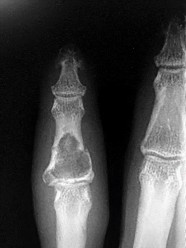

- الأشعة السينية (X-rays): هي الخطوة الأولى في تقييم الكسور، الخلوع، وتغيرات التهاب المفاصل. تساعد في تحديد مدى تدهور العظام والمسافات المفصلية. على سبيل المثال، تُظهر صور الأشعة السينية كسور السلاميات

أو كسور قاعدة العظم المشطي الخامس

، بالإضافة إلى علامات مثل "الدمعة الشعاعية" (Radiographic Teardrop) في الرسغ التي تمثل الزاوية الزندية الراحية الحرجة للكعبرة البعيدة

. - الأشعة المقطعية (CT Scan): توفر صوراً تفصيلية ثلاثية الأبعاد للعظام، وهي مفيدة جداً لتقييم الكسور المعقدة، مثل كسور العظم الخطافي (Hamate Hook Fracture) التي قد لا تظهر في الأشعة السينية العادية